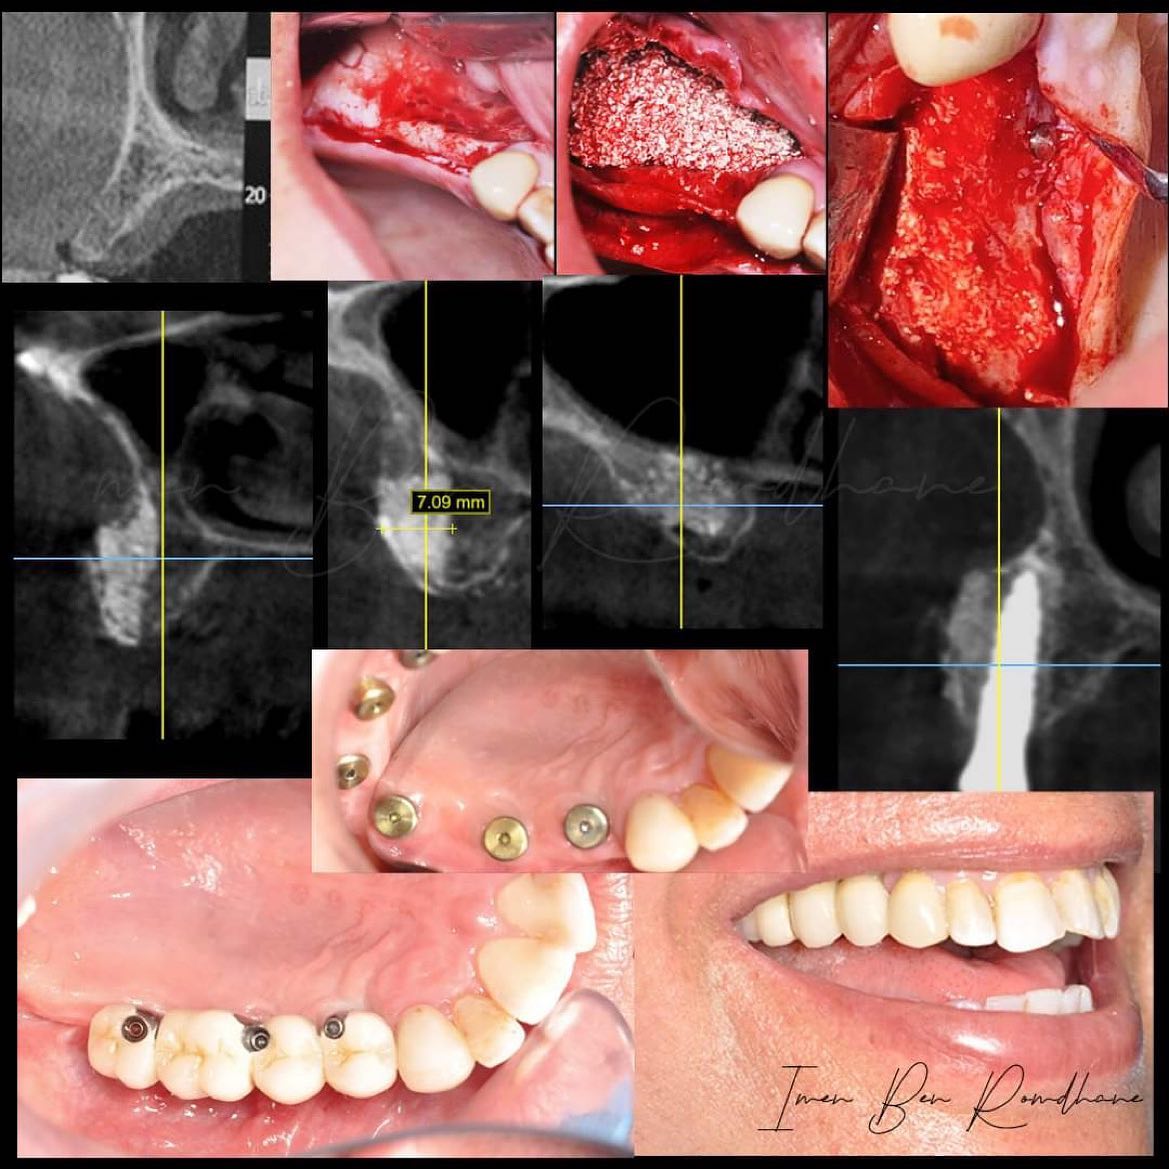

Augmentation osseuse horizontale avec la méthode dIstvan Urban

Augmentation osseuse horizontale avec la méthode dIstvan Urban sausage technique me permettant un gain horizontal de 7,09mm assurant une pose chirurgicale des implants prothétiquement guidés.

Greffe osseuse d’une zone esthétique maxillaire dune crête osseuse très résorbée classe 4 de Cawood avec une menbrane non resorbable PTFE renforcee titane

8 mois apres un implant straumann BLT 3,3/12 a été posé avec une première greffe de conjonctif enfoui. 4 mois après une temporisation a été faite avec une 2ieme greffe de conjonctif enfoui. 3 mois apres une couronne ceramo céramique sur un pilier zircone personnalisé a été ete réalisée